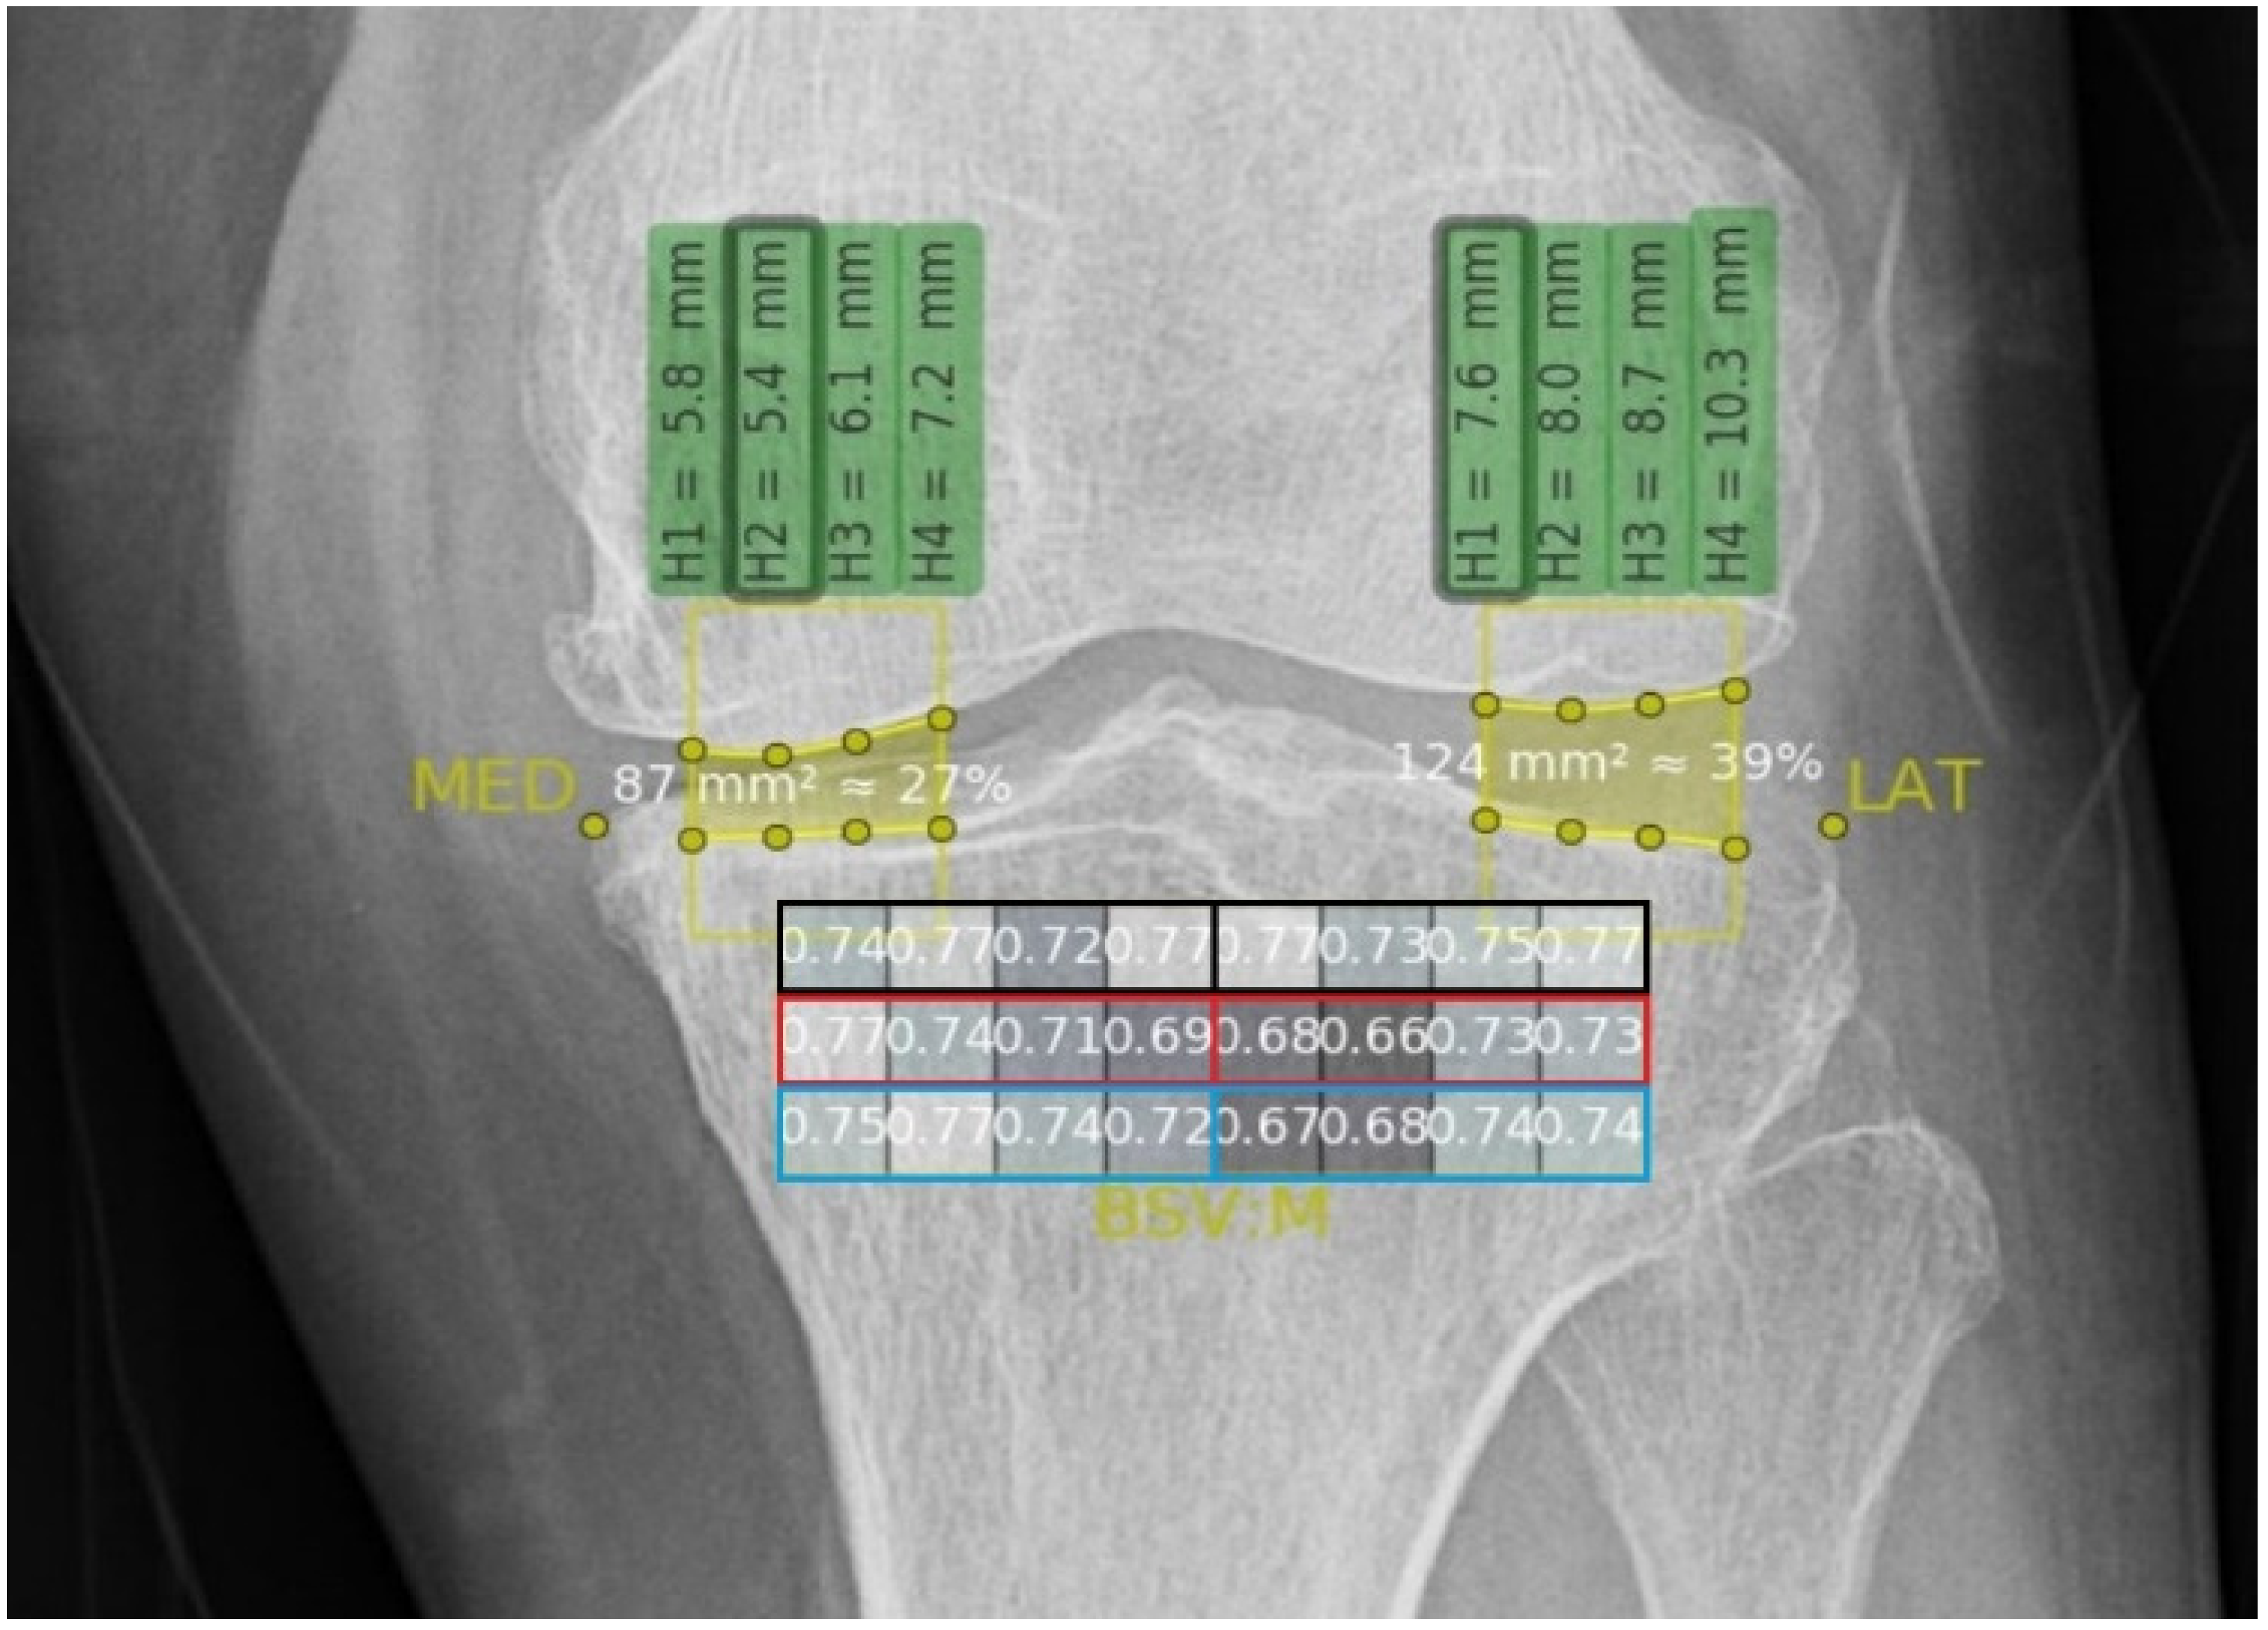

2.4.2. Texture Analysis

3.3. BSVs